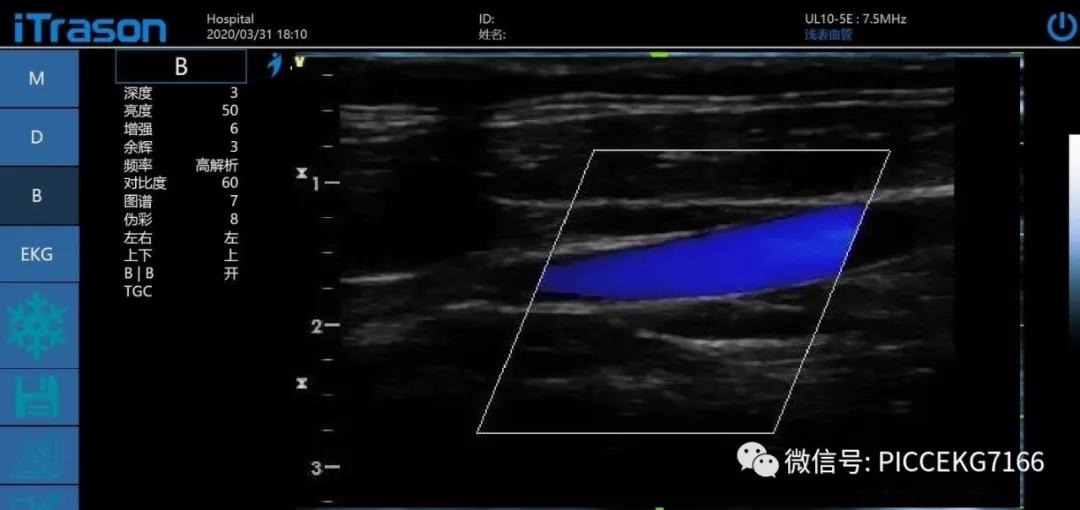

利用“动脉血为离心血,静脉血为回心血”为依据。具体操作如下(颈静脉和颈动脉为例): 血流方向:朝向探头流动的血流呈红色,背离探头流动的血流呈蓝色。并不是红色就一定是动脉,蓝色就一定是静脉,这个是重点:

如果将探头扫查方向倾斜指向患者同侧乳头,此时动脉的血流颜色应为蓝色,静脉血流应为红色。